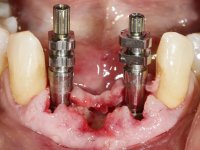

Após estudo imagiológico foi planificada a colocação de dois implantes de 3.3 mm de diâmetro e 10 mm de comprimento. No dia da cirurgia foram extraídos os dentes 42 e 32 e removido o implante. Os implantes foram colocados na zona dos alvéolos tendo o cuidado de lingualizar um pouco o seu posicionamento. Foi feita uma impressão pela técnica de moldeira aberta com o retalho aberto para a confeção da ponte provisória imediata. Enquanto a impressão foi para o laboratório, foram colocados parafusos de cicatrização altos e feita a sutura da ferida cirúrgica. A paciente esperou 2 horas na sala de espera enquanto no laboratório era confecionada a ponte provisória. A ponte provisória imediata aparafusada foi colocada e o seu assentamento controlado imagiologicmente. Passados 3 meses foi realizada a impressão definitiva com uma técnica de moldeira aberta. Nessa consulta aproveitamos para polir a ponte provisória com taças de borracha para que os tecidos moles pudessem maturar em melhores condições. Foi feita a recolha de informação para caracterizar da melhor forma a estrutura monolítica em Zr. Foram utilizadas guias de cor para a cerâmica de tonalidade coronária e gengival. No laboratório foi confecionada uma ponte em Zr. aparafusada que foi cuidadosamente caracterizada. Após aprovação pela paciente foi colocada definitivamente em boca. O aperto foi feito com uma chave dinâmica com 35 N de torque. Os orifícios foram tapados com teflon e obturados com resina composta.